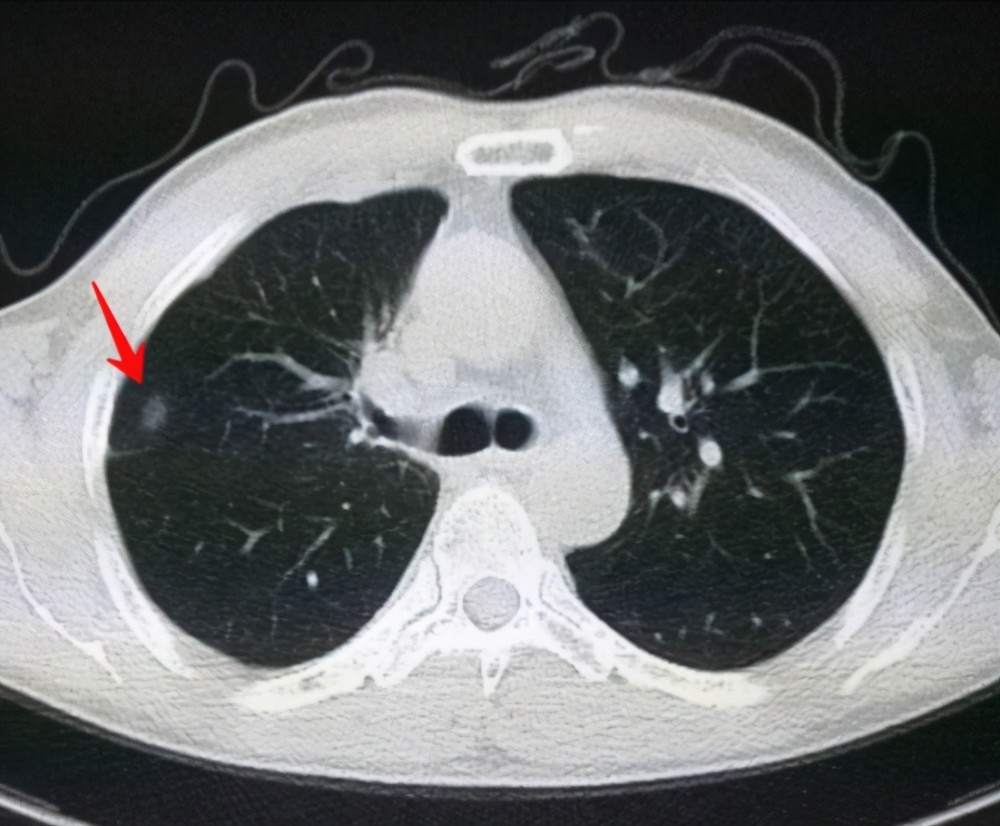

肺結節(jié)是一種常見的肺部疾病,其發(fā)病率逐年上升,雖然肺結節(jié)多數(shù)情況下是良性的,但也有可能惡化為肺癌,了解肺結節(jié)的形成原因對于預防和治療具有重要意義,本文將為您詳細解析肺結節(jié)的形成機制。

肺結節(jié)的形成原因

1、環(huán)境因素

環(huán)境因素是肺結節(jié)形成的重要原因之一,長期暴露于污染環(huán)境中,如空氣污染、化學污染等,可能導致肺部吸入有害物質,從而引發(fā)肺結節(jié),長期接觸石棉、硅塵等職業(yè)環(huán)境因素也可能增加肺結節(jié)的發(fā)病風險。

2、遺傳因素

遺傳因素也是肺結節(jié)形成的重要因素,研究表明,家族中有肺癌或肺結節(jié)病史的人群,其患病風險較高,遺傳缺陷可能導致肺部細胞異常增生,從而引發(fā)肺結節(jié)。

3、生活習慣

生活習慣對肺結節(jié)的形成也有一定影響,長期吸煙是肺結節(jié)形成的重要危險因素之一,煙草中的有害物質會對肺部造成損傷,導致肺部細胞異常增生,長期熬夜、飲食不規(guī)律等不良生活習慣也可能影響肺部健康,增加肺結節(jié)的發(fā)病風險。

4、免疫系統(tǒng)異常

免疫系統(tǒng)異常也可能導致肺結節(jié)的形成,免疫系統(tǒng)功能異常時,肺部可能無法有效清除感染、炎癥等刺激因素,導致肺部組織損傷和修復過程失衡,進而引發(fā)肺結節(jié)。